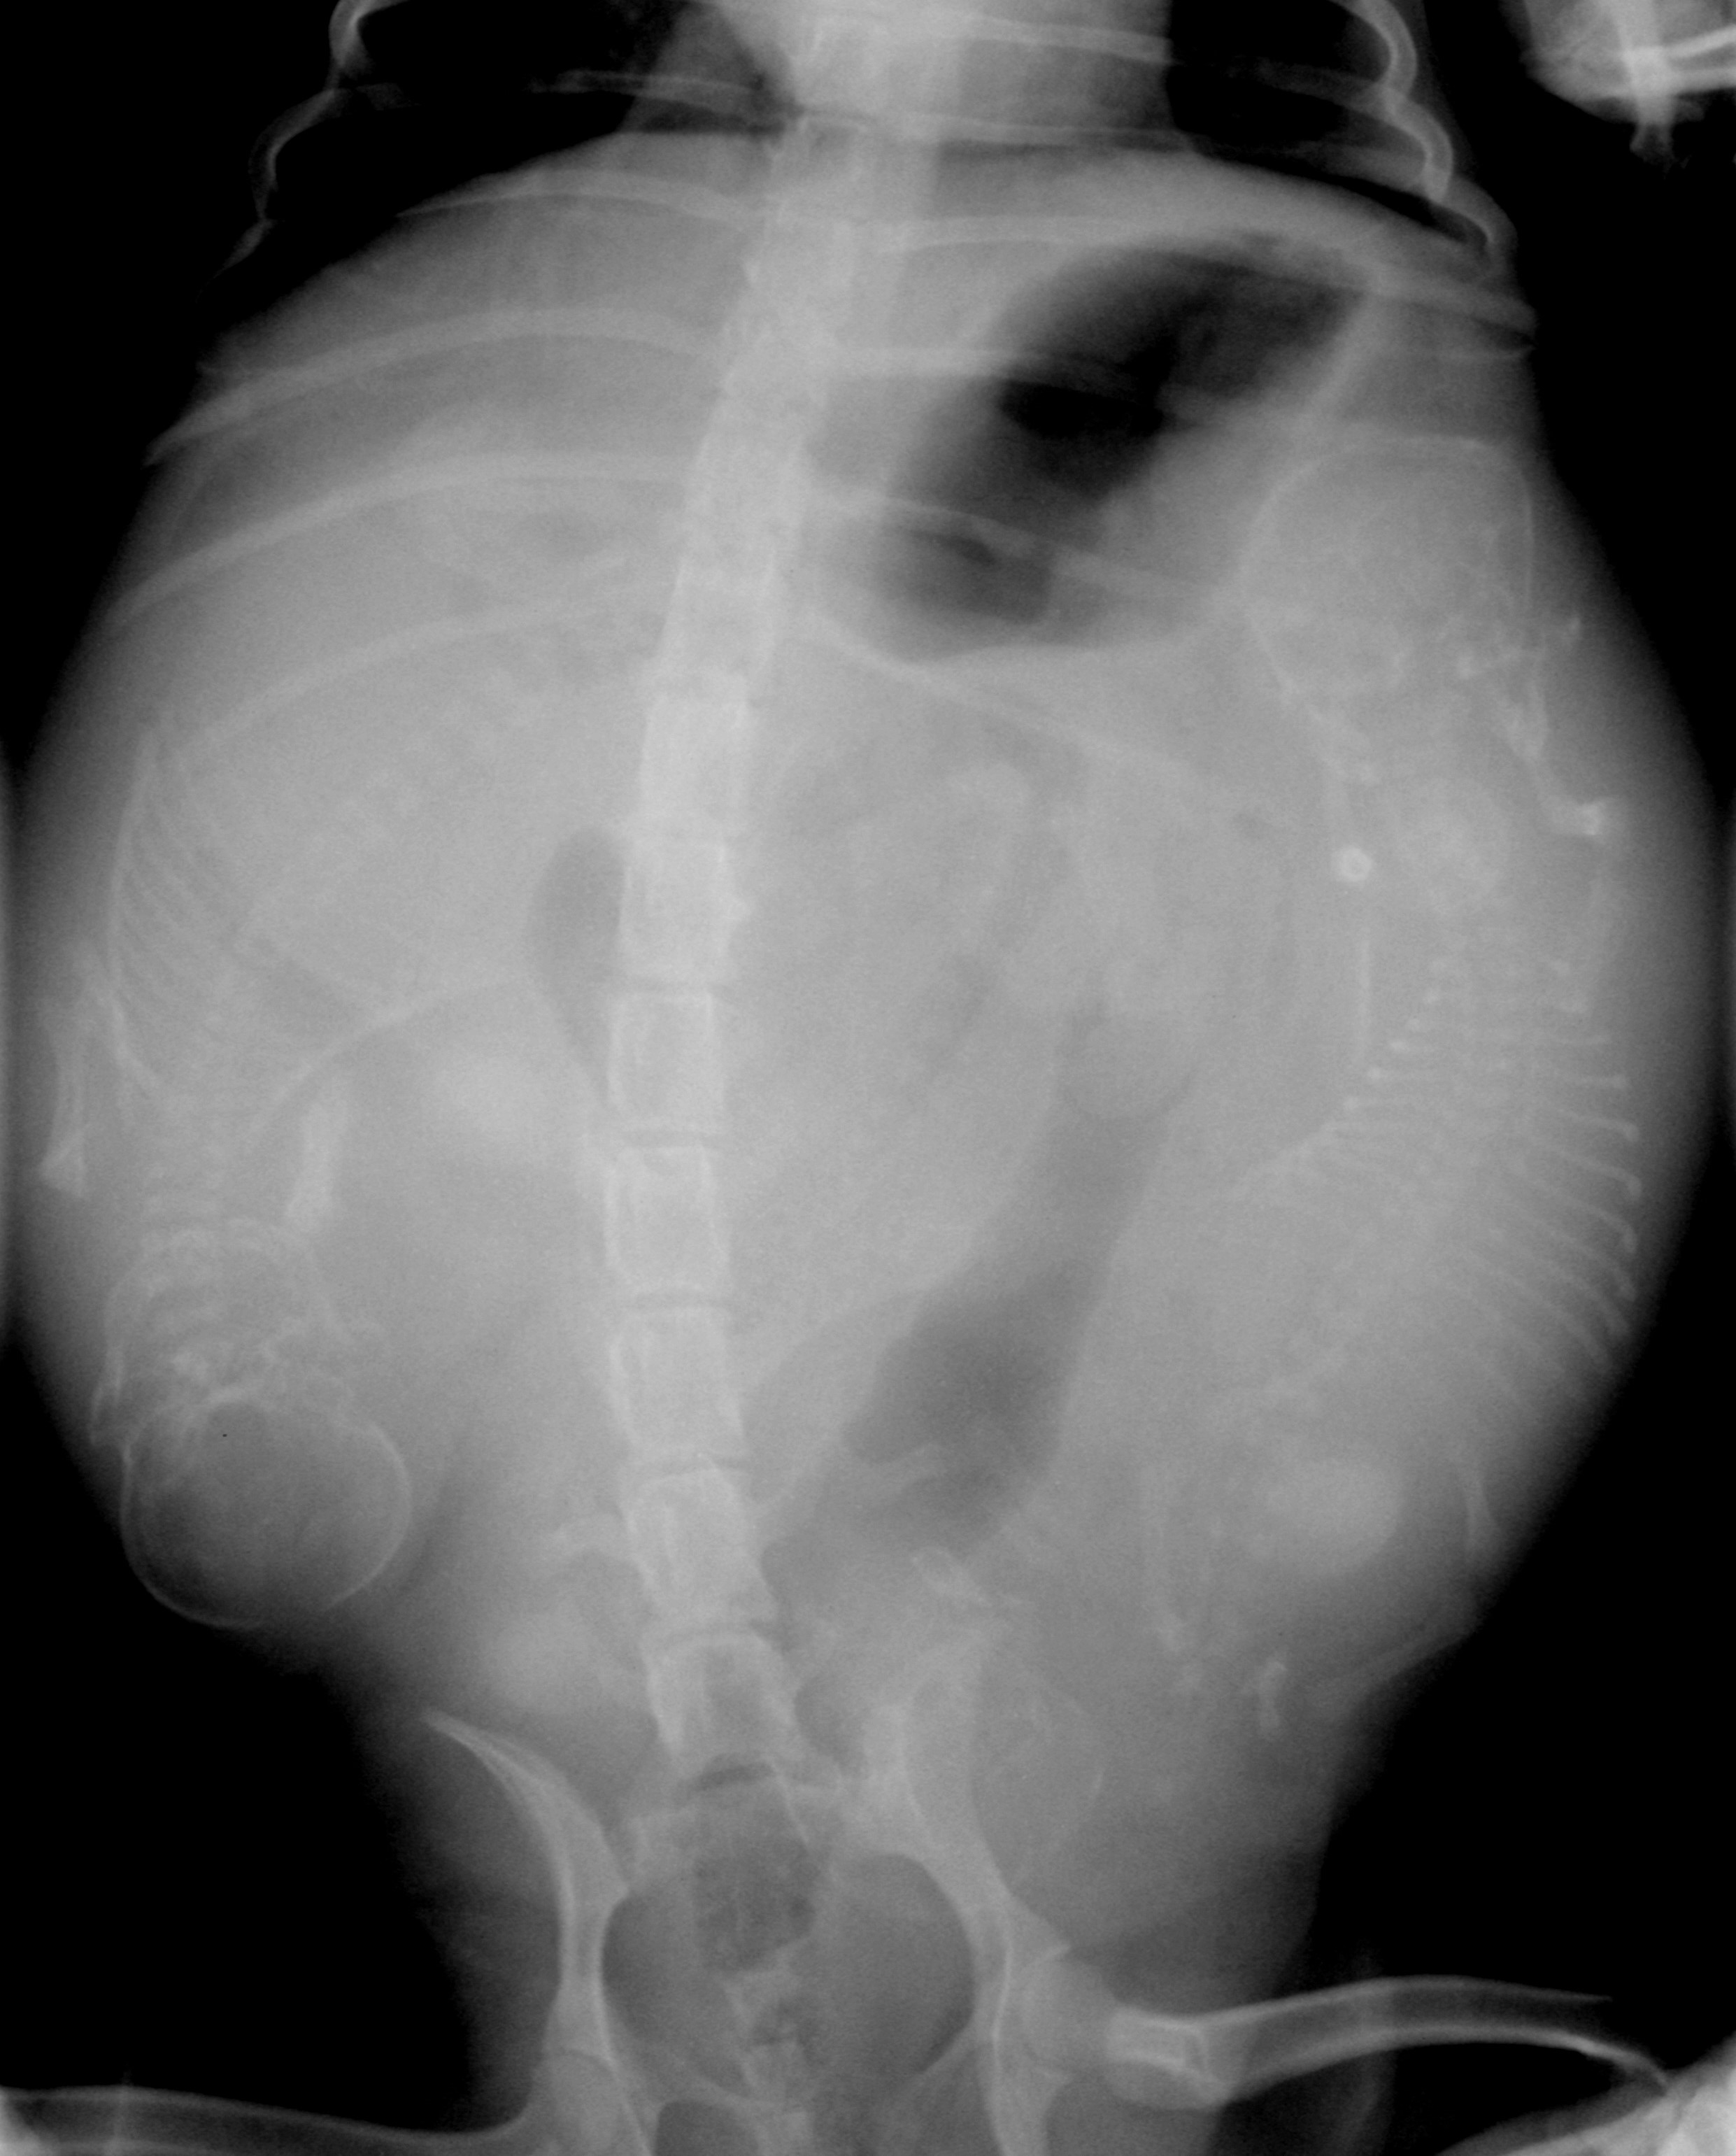

陰部からは羊膜の一部が露出しており、レントゲン検査にて3頭の子犬を確認しました。

↑お腹の中に3頭の子犬がいるのが確認できます